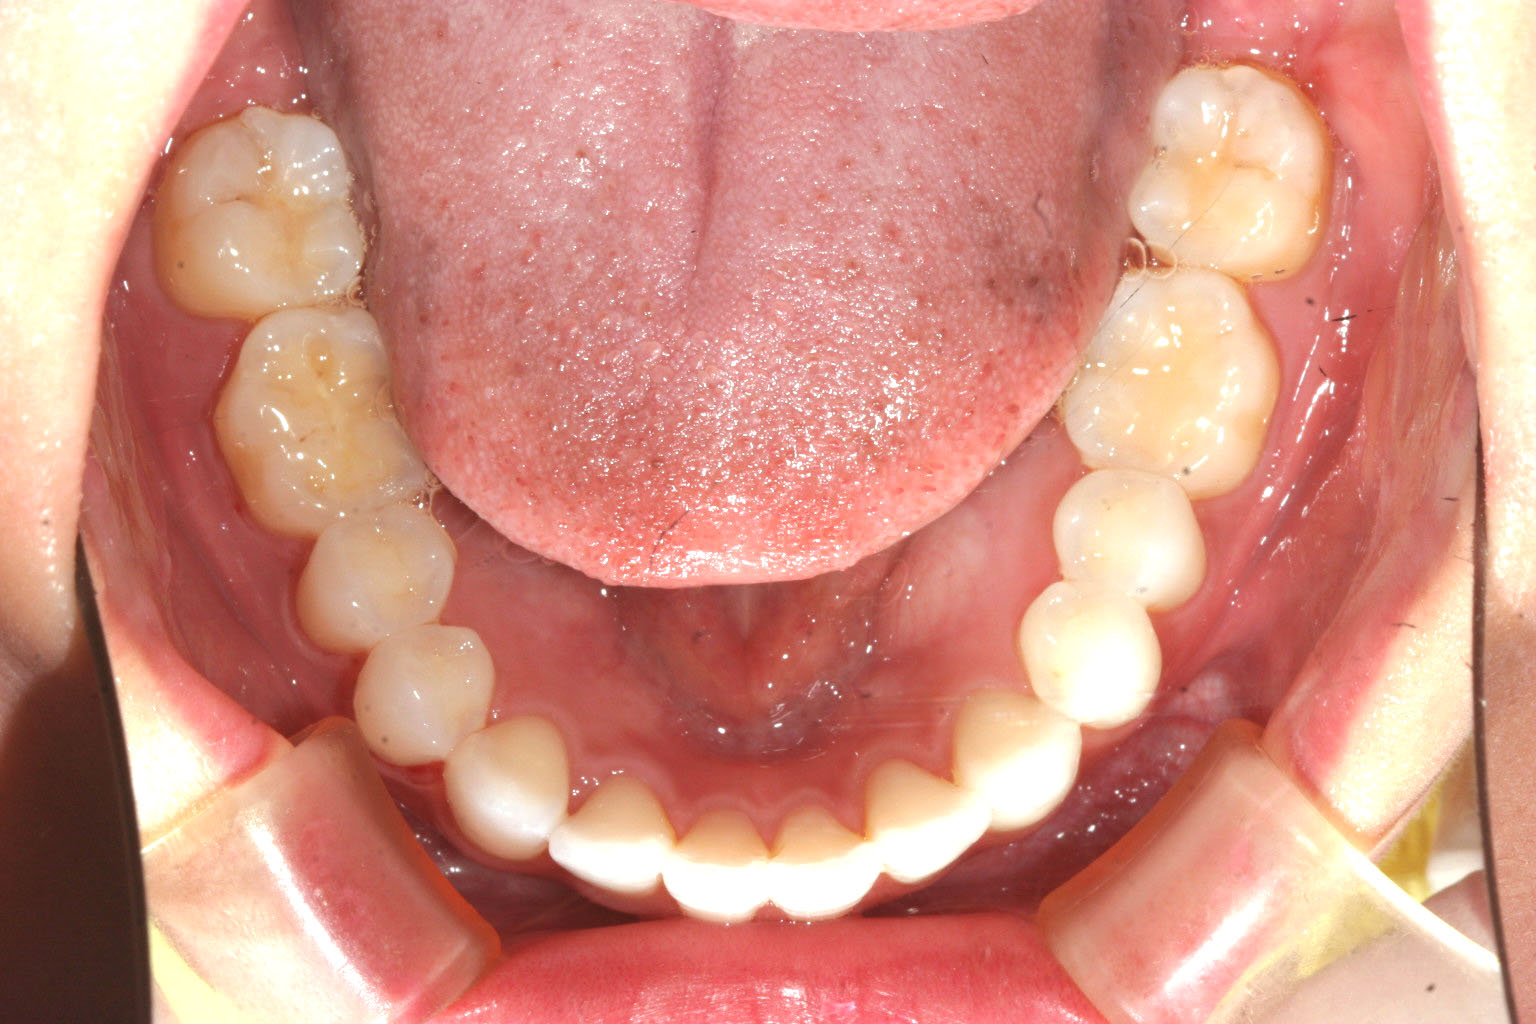

下顎にも少し叢生が見られます。

下顎もバッチリですね!